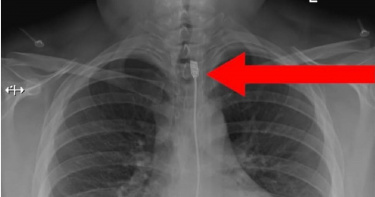

聖誕節快到了,許多人會在家中擺放聖誕樹和飾品,路上也到處可見張燈結綵。沒想到,國外流行拿聖誕飾品當「性玩具」的趨勢,對此專家呼籲不要這樣做,並警告危險後果。英國一名婦產科醫師莎拉(Sarah Welsh)是保險套品牌的共同創始人,她向《NeedToKnow.Online》透露,近來有很多人會把聖誕飾品當玩具,「這種趨勢是個壞主意」,甚至因此住院,顯然對健康有害,因為聖誕飾品可能較鋒利,過程中若破裂,會導致疼痛、受傷的風險,莎拉警告人們不要拿聖誕飾品當玩具使用。(圖/翻攝自hanxofficial IG)即使只是糖果,也可能有危險,莎拉指出基於衛生問題和含糖量,任何含糖的東西,都應該遠離下體,否則會破壞陰道微生物群的脆弱生態系統,容易感染陰道鵝口瘡(念珠菌)。病患把拐杖糖當成玩具,結果拿不出來。(圖/翻攝自Savage Paramedics臉書)然而,把聖誕飾品當成性玩具的情形,比想像中普遍,2013年有一項案例研究提到,有民眾將玻璃飾品塞進體內,也有護理人員在臉書群組分享患者使用拐杖糖的「傑作」,以及X光照片,清楚可見一根拐杖糖和一個聖誕樹裝飾球卡在直腸裡。聖誕樹裝飾球卡在體內。(圖/翻攝自Savage Paramedics臉書)事實上,英國光是去年,年齡25至64歲的民眾,就發生13213起「聖誕飾品塞進體內」的案例。莎拉提醒,市面上有很多合適,且經過認證的性玩具,是比聖誕飾品更好的選擇。